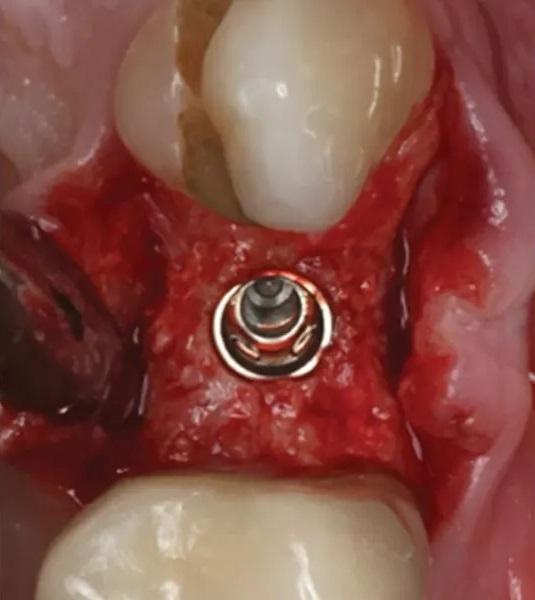

Фото 15. Окклюзионный вид гребня непосредственно после установки имплантата.